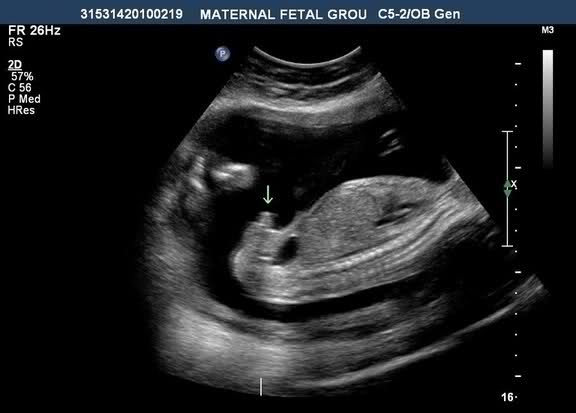

This is at 15 weeks...getting mixed reviews of boy and girl. No potty shot but looked to be nothing down there when the tech looked, just the nub on profile. Thanks :)

Hmmm- by 15 weeks I don't think there is a nub anymore. So I'm going to guess this is a boy

I would vote boy on the top picture.

15 weeks is to late for a nub guess, you need a potty shot!! It does look rather like a boy though!

I don't have any potty shots because the tech didn't print them out. She insisted this stage was too early although I did not see anything protruding on the potty shot so when I saw the "nub" on profile I was confused. Other techs have been telling me a prominent clitoris is common at 15 weeks and that the angle of my babies nub looks girly as well as the shape but I'm still not sure :think:

I have seen this type of question posted a number of times on IG. The tech there always says that you can clearly see a penis and scrotum pointing straight up at 15 weeks, and that profiles are a great way to identify sex, particularly before the baby gets too squished (so, you definitely don't need a potty shot to identify sex). Even if you look at the last pictures on the site below (which are 14 weeks), yours is almost identical to the girl picture: Embryo Development external genital sex organs - angle of the dangle boy or girl ultrasound gender scan - Baby2see

Personally, I would see check out 15 week ultrasounds on youtube, and I think that you will find that the boy profiles look very different ;)